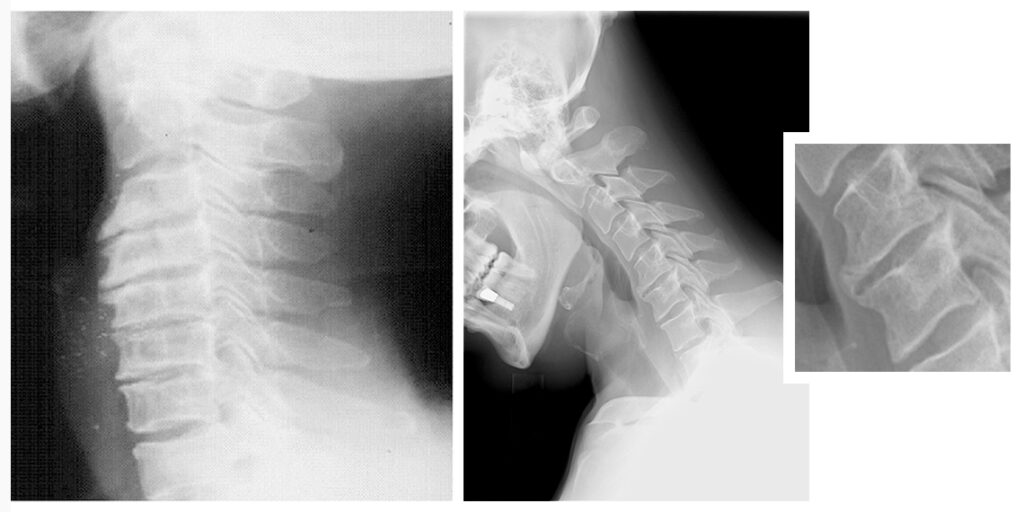

Servikal omurga; diskler, bağ dokular, kaslar ve sinirlerle desteklenen kompleks bir yapıdır. Zamanla bu yapıların elastikiyeti azalabilir, diskler yassılaşabilir, eklem yüzeyleri bozulabilir. Bu değişiklikler bir araya geldiğinde, halk arasında “kireçlenme” olarak bilinen tablo ortaya çıkar.

Fizyoterapi açısından ise bu sadece bir yapısal yıpranma değil; kas-sinir koordinasyonunun bozulması, hareket kalitesinin düşmesi ve vücudun koruyucu reflekslerle kendini kısıtlaması anlamına gelir.